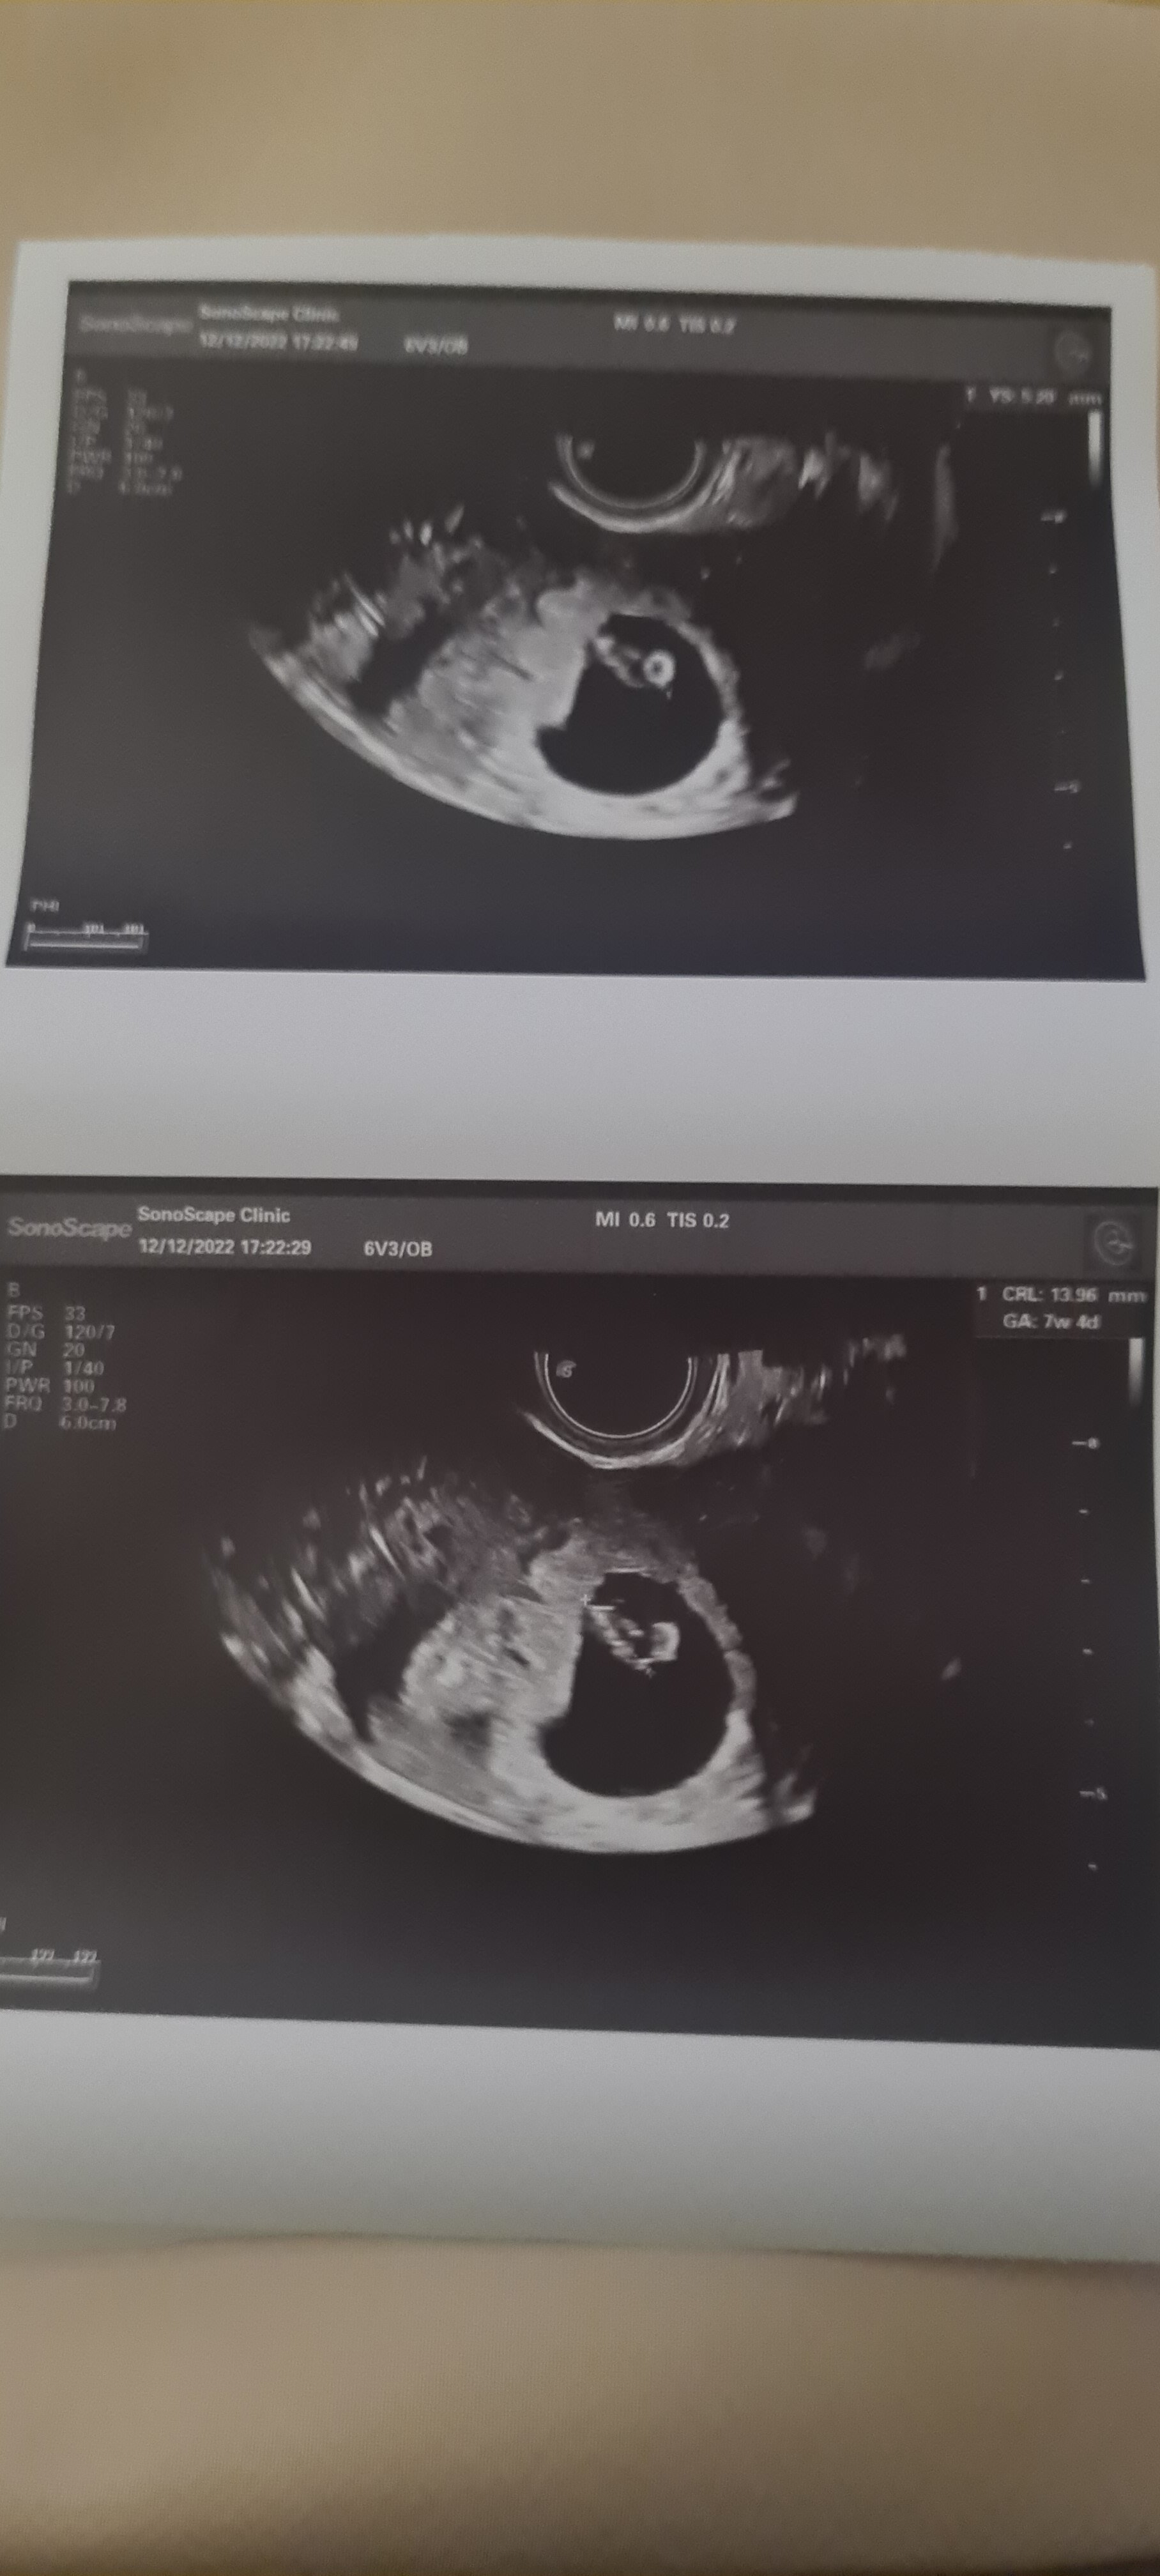

wg. om 7w6d wg. usg 7w4d. Termin porodu na 28 lipca. Karta ciąży założona, skierowanie na badania prenatalne wypisane. Przesyłam foto mojego Mini Bobasa